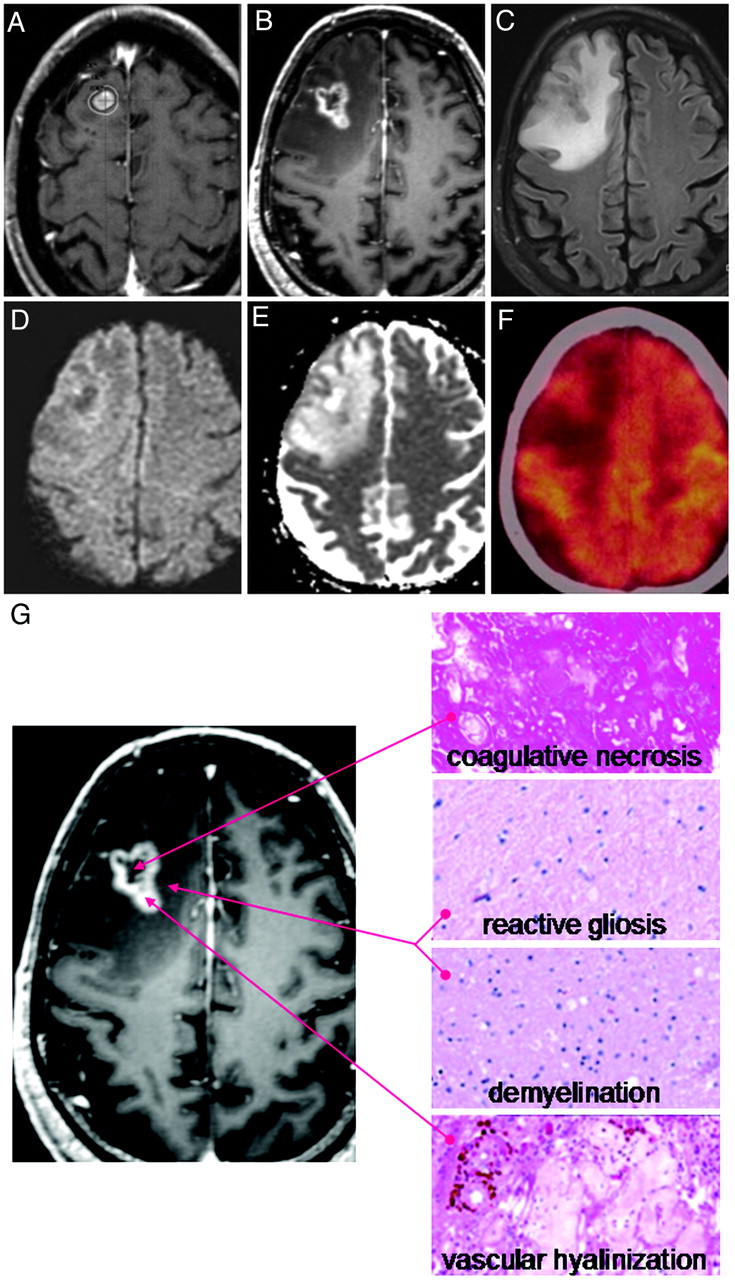

Of note, 10 lesions required salvage surgery due to focal neurologic deficits caused by increased lesional size and surrounding edema. Histopathology in all cases demonstrated a significant inflammatory infiltrate with central necrosis, consistent with radiation-induced necrosis (Fig 5).

Example of radiologic and histopathologic changes in enlarging lesions. A, Gamma Knife treatment plan for a 56-year-old man with metastatic melanoma. The lesion was treated with 22 Gy to the 50% isodose line. B, Twelve-month follow-up T1 postcontrast MR imaging. C, Twelve-month FLAIR image. D and E, Twelve-month DWI/apparent diffusion coefficient images, respectively. F, Twelve-month FDG-PET image. G, Histopathology from stereotactic image-guided biopsies of the lesion. Specimens from the central, T1 hypointense portion of the lesion demonstrate coagulative necrosis. Specimens from the peripheral, T1 hypointense portion of the lesion demonstrate reactive gliosis and demyelination. Specimens from the T1 contrast-enhancing portion of the lesion demonstrate vascular hyalinization. This constellation of histopathologic findings suggests a diagnosis of radiation-induced changes.